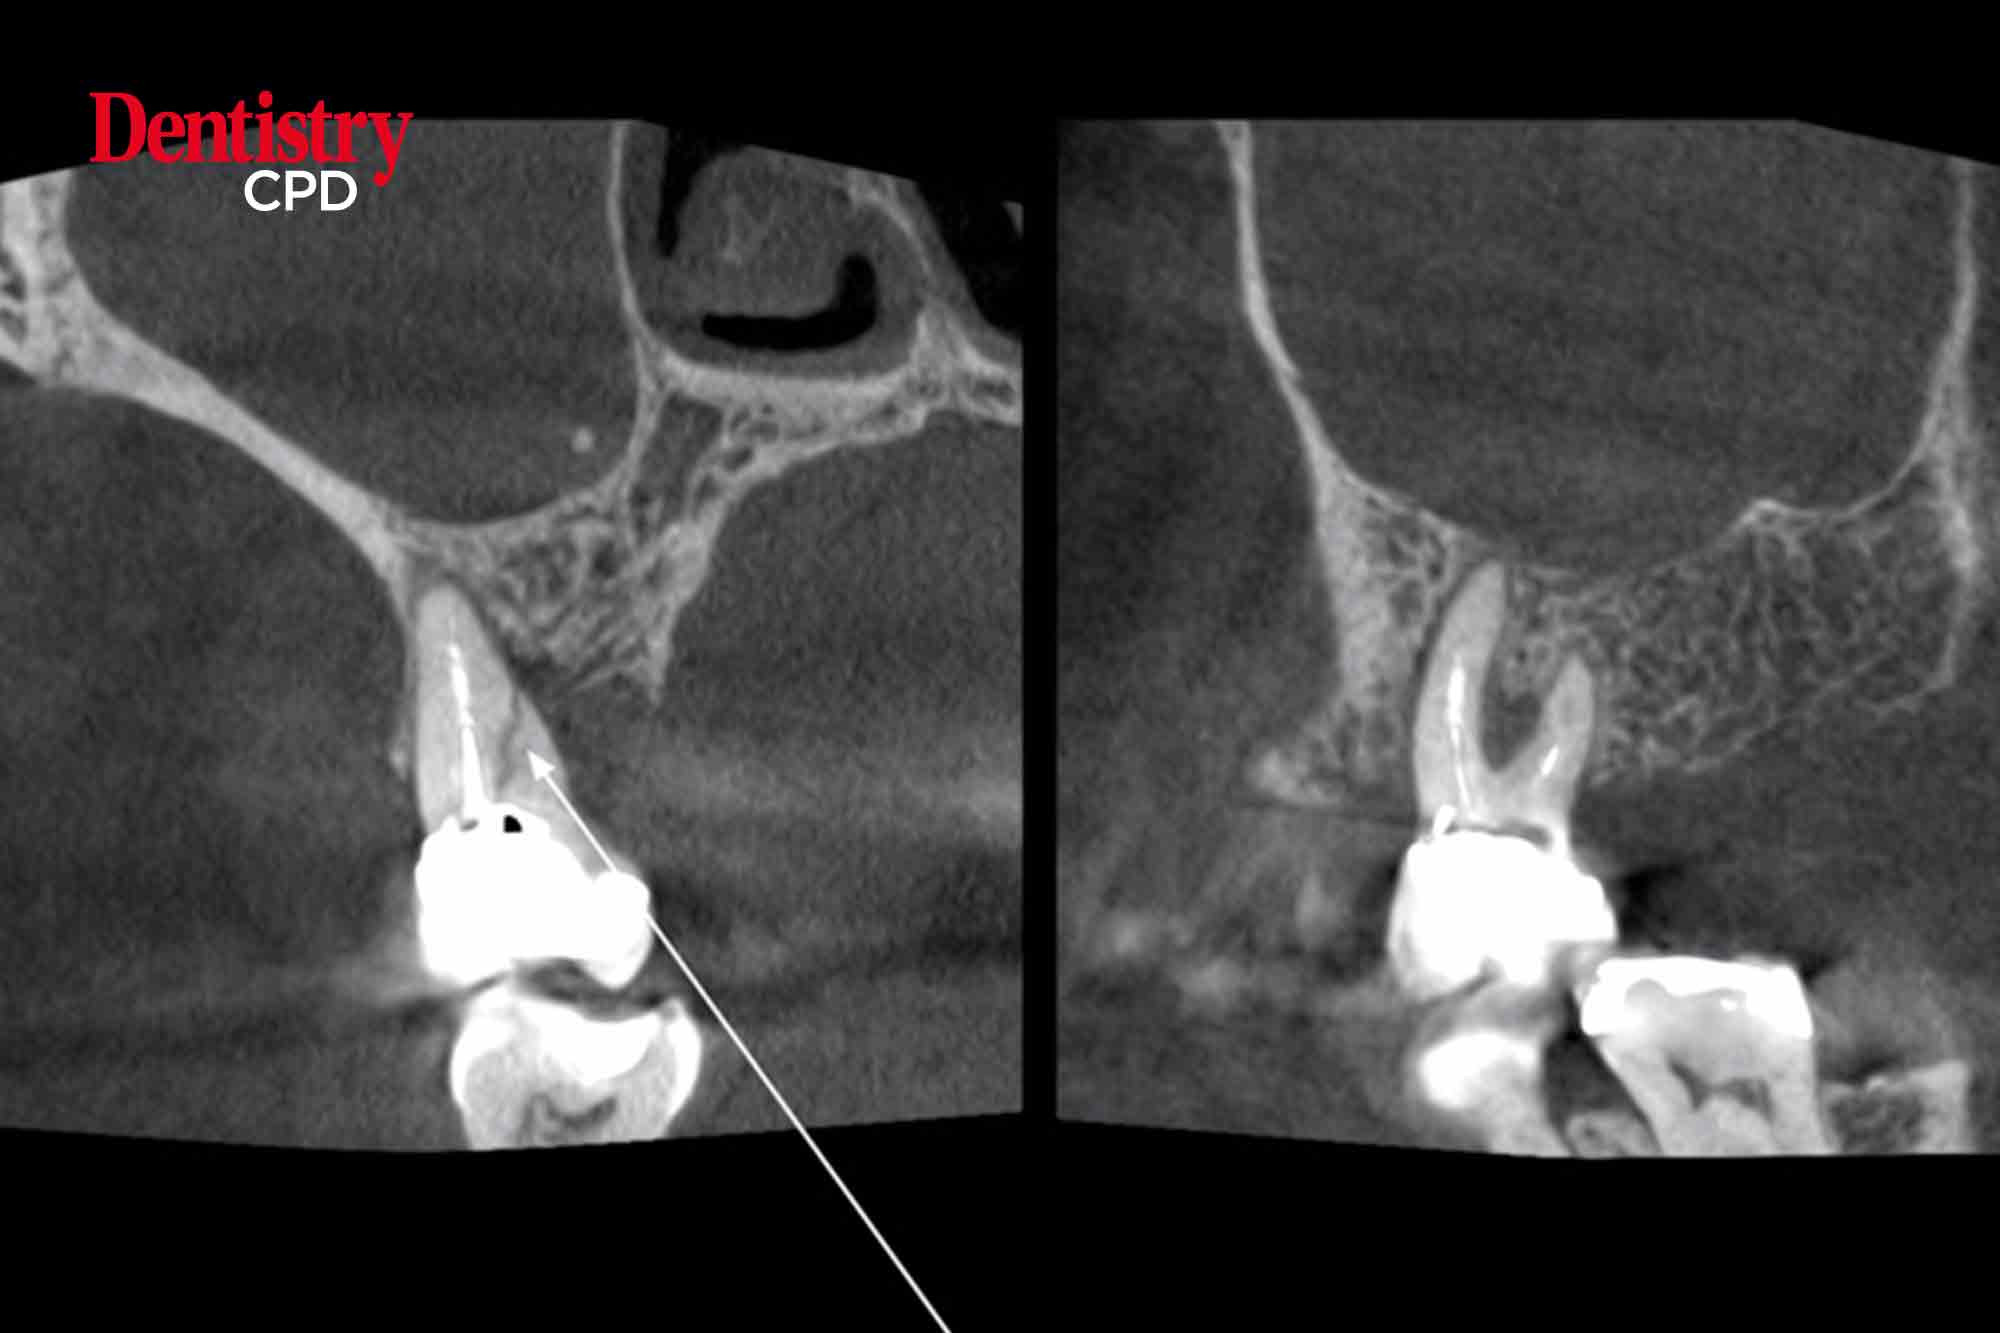

Identification, diagnosis and management of cracks

John Rhodes looks at the identification, diagnosis and management of cracked teeth in endodontics